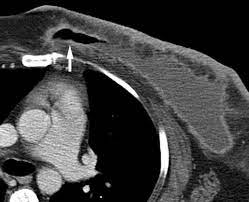

Does Ct Scan Detect Breast Cancer : Breast Masses Cancerous Tumor Or Benign Lump : One example is a combined pet and ct scan (known as pet/ct), available.. The whole appointment can take up to an hour and a half depending on which part of your body they are scanning. A ct scan can show whether breast cancer has spread to the lungs or liver. It can also show changes caused by other medical conditions. Ct scans and cat scans describe the same imaging test. Ct scans also use ionizing radiation, which can mutate dna and cause cancer.

Ct Abnormality In Patient With Stage Ii Breast Cancer History from cdn.sanity.io Ct scans also use ionizing radiation, which can mutate dna and cause cancer. One example is a combined pet and ct scan (known as pet/ct), available. How many cancer deaths caused by unnecessary ct scan are occurring now? Staging and treatment of breast cancer. What you need to know. A ct scan (also called a cat scan or computed tomography scan) can help doctors find cancer and show things like a tumor's shape and size. Ct scans can detect bone and joint problems, like complex bone fractures and tumors. The whole appointment can take up to an hour and a half depending on which part of your body they are scanning.

Breast cancer type and stage: Interventional radiologists, physicians who specialize in minimally before a pet/ct scan, an iv that injects a small amount of a radioactive substance will be placed into one of your veins. Pet scans, short for positron emission tomography, can detect areas of cancer by obtaining images of the body's cells as they work. Routine body scans, whether mri, ct or pet scan should not be done for asymptomatic screening with the exception of low dose ct scanning of the lungs in recent or why aren't pancreatic ct scans used in routine physical examinations to detect and prevent the spread of pancreatic cancer? Ct examination of the pancreas should always be done with maximum amount of contrast at a maximum flow rate, because both on a poor quality scan it is impossible to rule out emboli. A radiographer operates the scanner. Can be detected as early as possible. It does a better job of identifying a small mass in a woman's. Ct scans can be used to identify disease or injury within various regions of the body. Your healthcare provider will order a ct scan to help make a some risks associated with ct scans include: The pet scanner detects signals that are given off from the tracer. Exposure to ionizing radiation is. The whole appointment can take up to an hour and a half depending on which part of your body they are scanning.

Best Scans To Detect Cancer Envision Radiology from www.envrad.com Cat scan stands for computed axial what does a ct scan show? Can you see cancer on a ct scan or mri? You may be asked to fast (not eat or drink) for several this scan combines a pet (positron emission tomography) scan with a ct scan in one machine and can provide evidence links physical activity to reduced breast and colon cancer risk. How many cancer deaths caused by unnecessary ct scan are occurring now? Ct scans can detect bone and joint problems, like complex bone fractures and tumors. By comparing ct scans done over time, doctors can see how a tumor is responding to treatment or find out if the cancer has come back after pet scan: We prefer to scan from bottom to top, because if a patient can't hold his. What does a cat scan tell you?